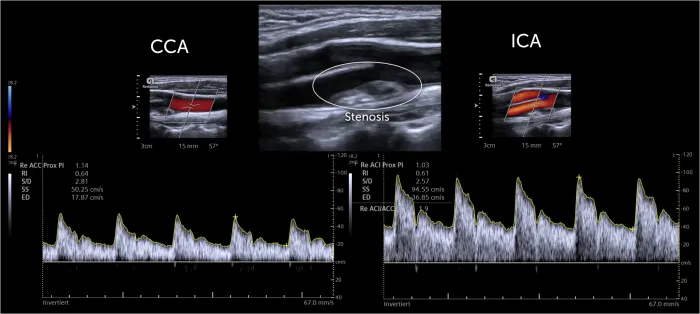

Vascular Applications - Vessel Voyagers

- Carotid Arteries: Stenosis grading.

- PSV $\textbf{>125 cm/s}$ for $\textbf{>50%}$ stenosis.

- PSV $\textbf{>230 cm/s}$ for $\textbf{>70%}$ stenosis.

- ICA/CCA ratio, EDV also assessed.